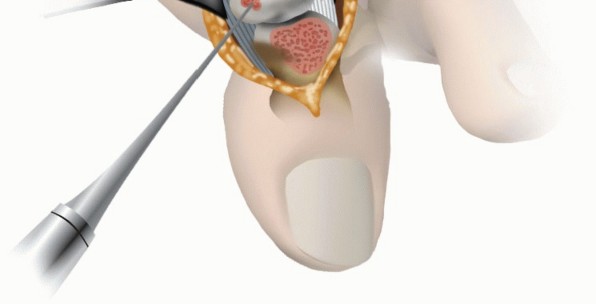

7. Microfracture

The remaining cartilage lesions at the first MTP joint or the proximal phalanx must be débrided of all remaining unstable cartilage and fibrous tissue.

The calcified cartilage layer must be completely removed.

Using an awl, the microfractures are placed approximately 1 to 2 mm apart and about 2 to 4 mm deep (TECH FIG 4).

Illustration 9 for Mastering Extensive Plantar Release for Hallux Rigidus

8. TECH FIG 4 • Microfracturing of the metatarsal head.